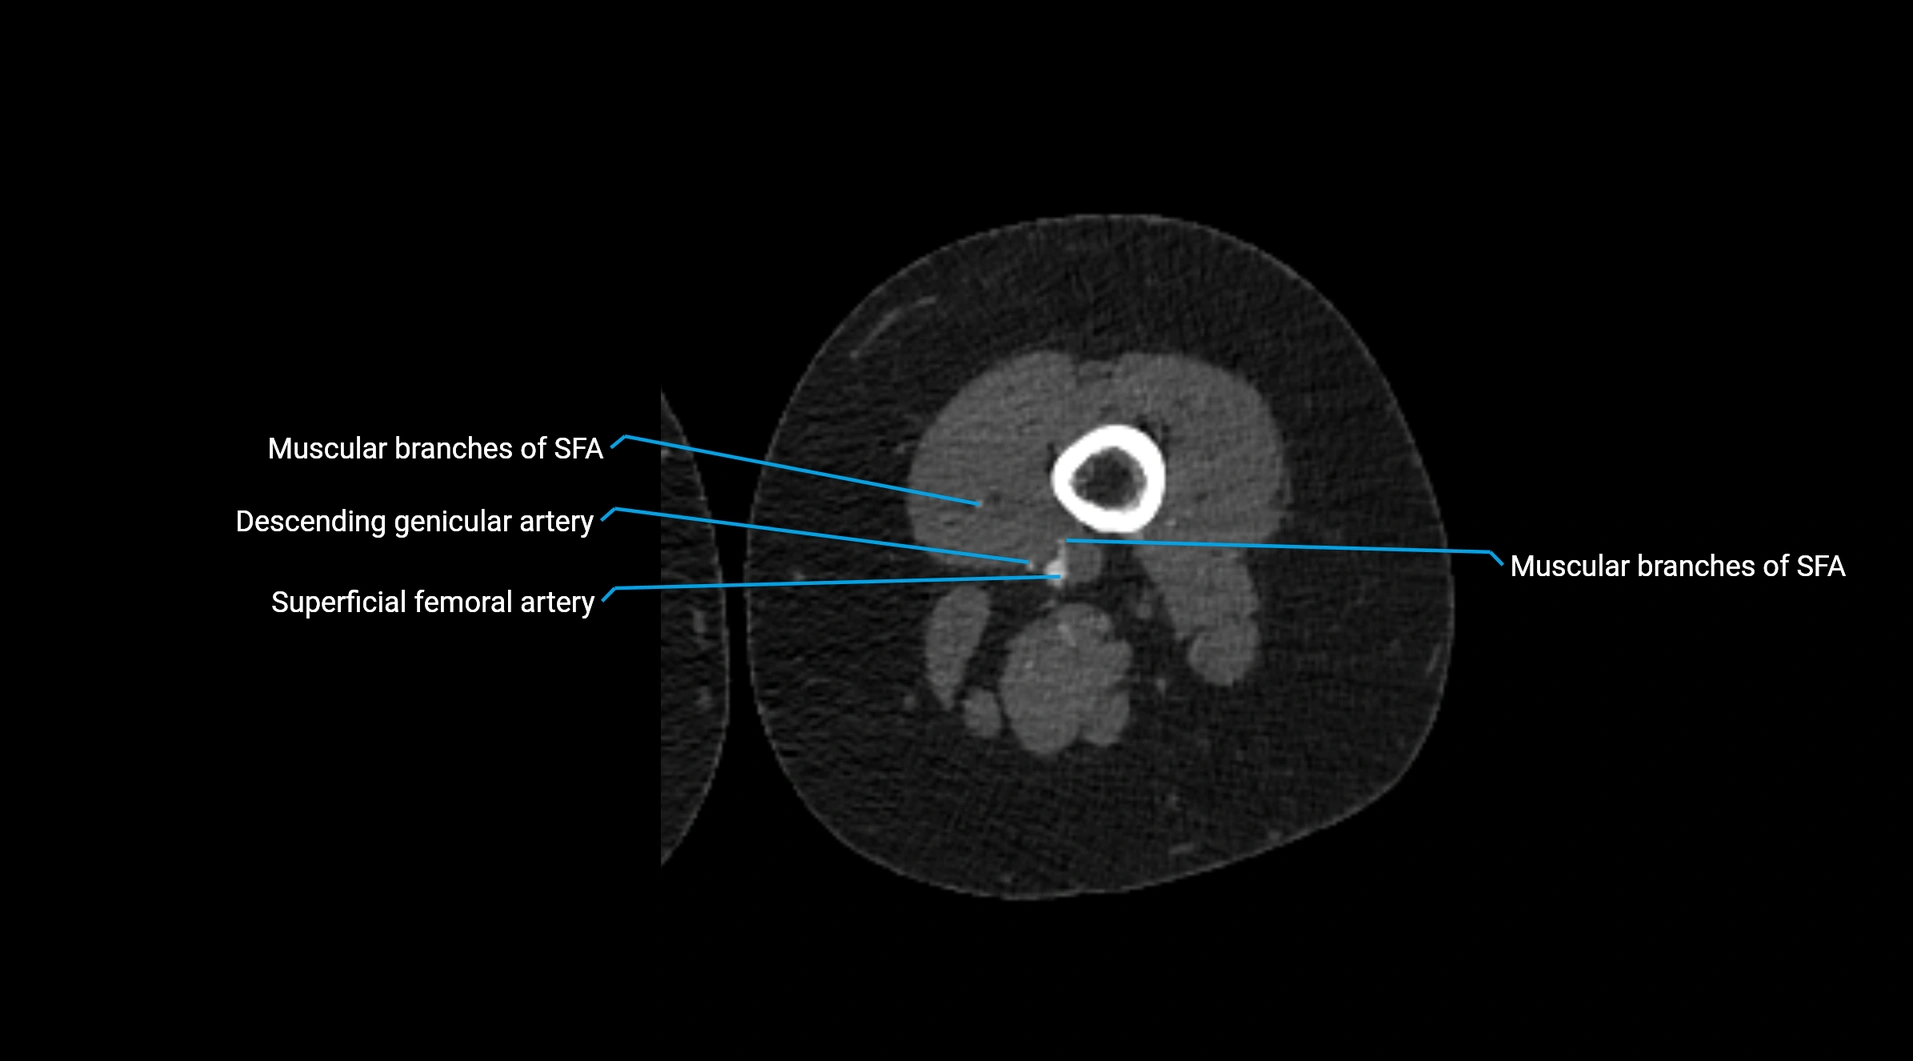

Contrast-enhanced CT (CTA):

• Gold standard for abdominal aortic imaging

• Provides excellent detail of lumen, wall, aneurysm, thrombus, and branch vessels

• Multiplanar and 3D reconstructions help in aneurysm measurement, stent graft planning, and dissection evaluation